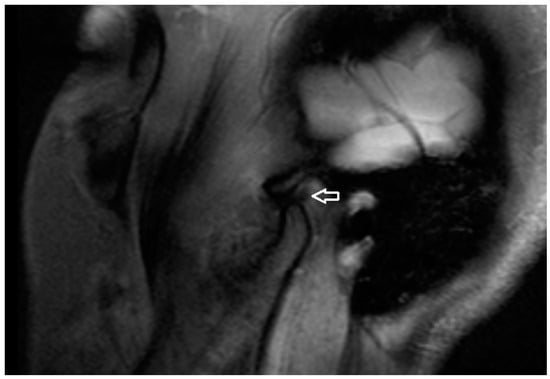

In the US analysis, we aimed to assess synovial effusion within the joint, which is indicative of inflammation or pathological fluid accumulation (Figure 2). Additionally, a thorough examination of the osseous structures was conducted. This included identifying the presence of osteophytes and evaluating any erosive changes to the bone surfaces. Furthermore, the analysis extended to the evaluation of the articular disc (Figure 3). For the purposes of the study, a unique research protocol was proposed, consisting of the assessment of the temporomandibular joint in the neutral position (mouth closed) with the mouth in maximum opening and the assessment of the path of the articular disc movement in a dynamic test. All examinations were performed by the same experienced radiologist using a LOGIQ E10 ultrasound with a dedicated L8-18i hockey stick linear probe (GE Healthcare, Boston, MA, USA).

Figure 2. Ultrasound (effusion within the joint).